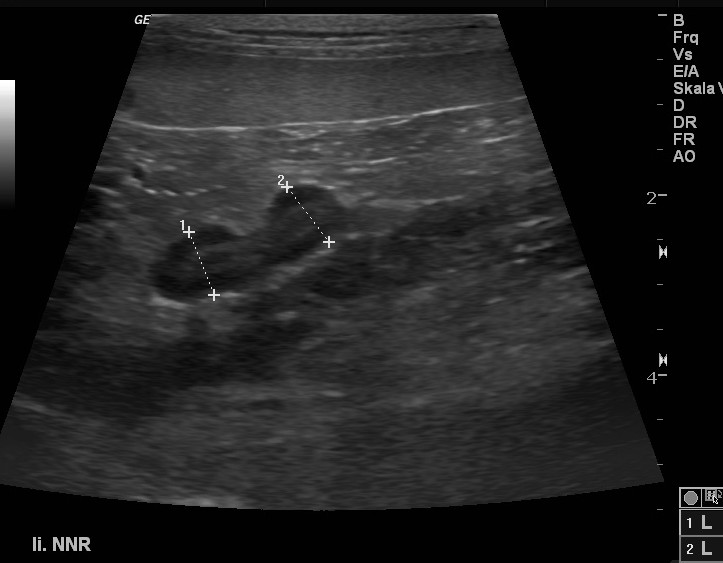

Niere und Harnableitendes System

Akute- und chronische Erkrankungen der Blase- und der Niere werden nicht selten unterschätzt. Einen Funktionsverlust der Nieren kann man im Akutfall nur mit sofortiger intensiver Therapie beheben und den chronischen Funktionsverlust nur Aufhalten jedoch selten noch ausheilen. Harnstoff und Kreatinin sind Funktionsparameter der Niere die erst verändert sind, wenn 80% des Nierengewebes bereits funktionslos geworden sind. Frühere Marker sind der SDMA-Marker und die UPC.

![]() |